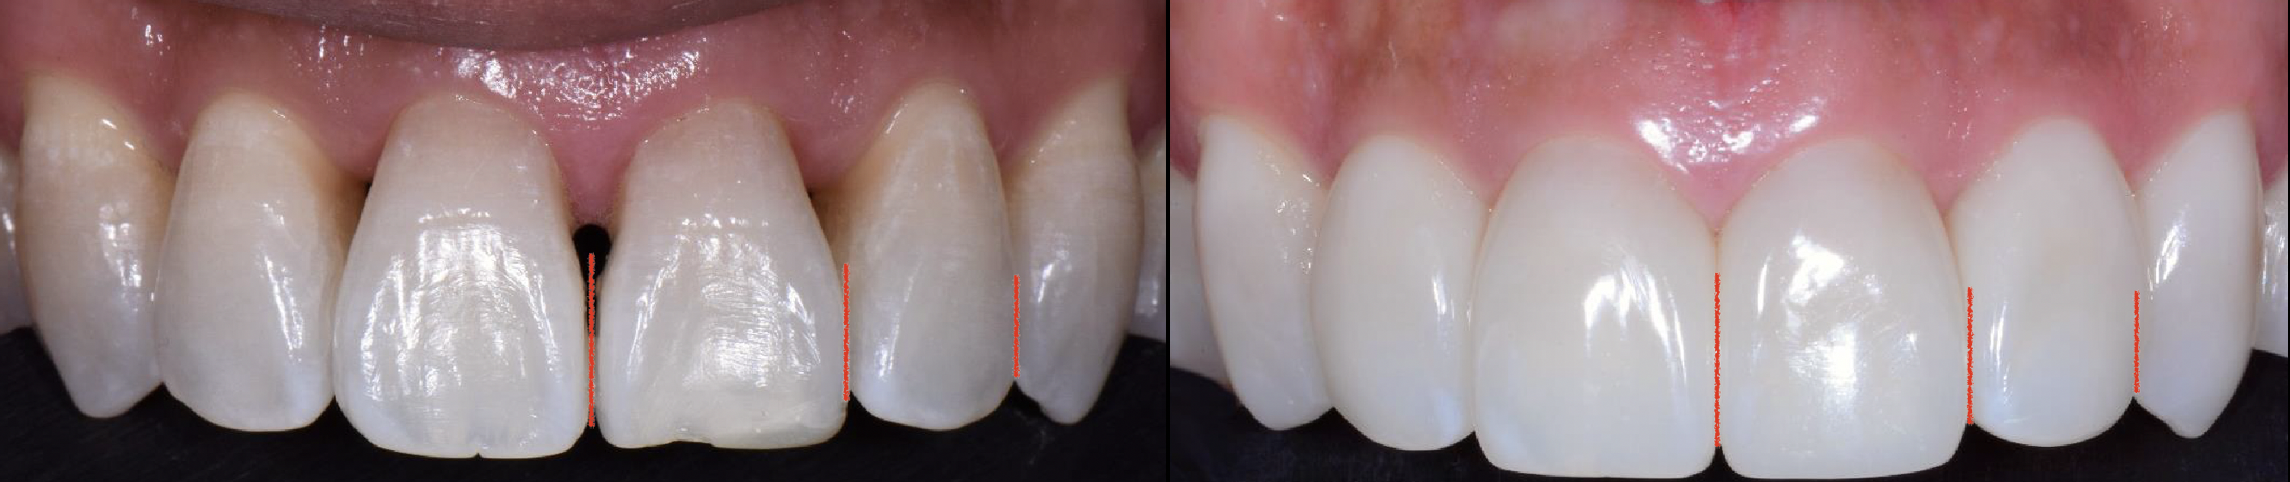

Fig 3. Injection molding, preoperative (left) and postoperative (right) images. The stark contrast of black and white is more visually noticeable than the soft contrast of pink and white.

Figure 3

Injection molding with warmed composite is a noninvasive, additive treatment that requires no tooth structure removal. Anatomic Mylar matrices in the difficult to polish subgingival and interproximal areas create smooth contours favorable for tissue adaptation and health. An advantage of the Mylar finish is reduced biofilm and stain accumulation, with any calculus easily removed. Injection molding creates broad incisal gingival and buccolingual contacts that can lend orthodontic stability. Longer contact lengths may result. However, soft color contrasts of pink tissue against white tooth are less visually distracting than the stark contrasts between white teeth and black triangles (Figure 3).6